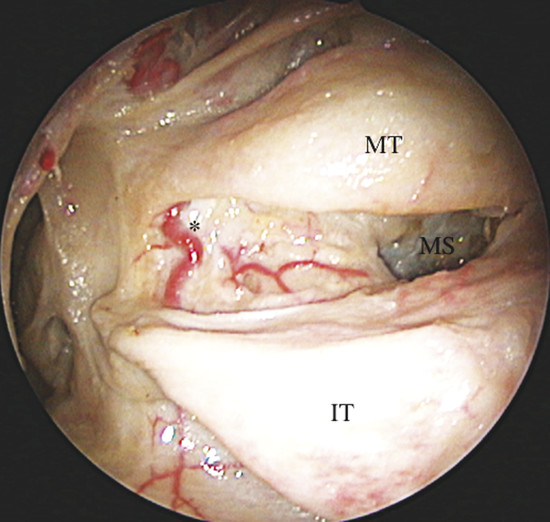

It gives off two main branches, the posterior lateral nasal artery (PLNA) and the posterior septal artery (PSA), 1 , 2 which can be divided into one or two trunks medial to the ethmoidal crest, before or after crossing the sphenopalatine foramen. It is rarely possible to identify more than two trunks. 1 , 3 The PLNA supplies the region of the lateral nasal wall giving off branches to the inferior turbinate (inferior turbinate artery), middle turbinate (middle turbinate artery), mucosa of the fontanelle, and to the mucosa of the maxillary sinus 4 (Fig. 3‑3, Fig. 3‑4). In approximately 20% of cases this artery supplies the superior turbinate. 5 The inferior turbinate artery enters a bony canal and runs anteriorly along the turbinate. It usually gives off two terminal branches, within or adjacent to the bone, supplying the mucosa of the turbinate (Fig. 3‑5). The artery gives off several small vessels to the maxillary sinus and to the ethmoidal complex. The middle turbinate artery gives off several branches, some of which run along the medial surface of the turbinate whereas the other branches supply the lateral turbinate surface and anterior ethmoidal complex (see Fig. 3‑3).